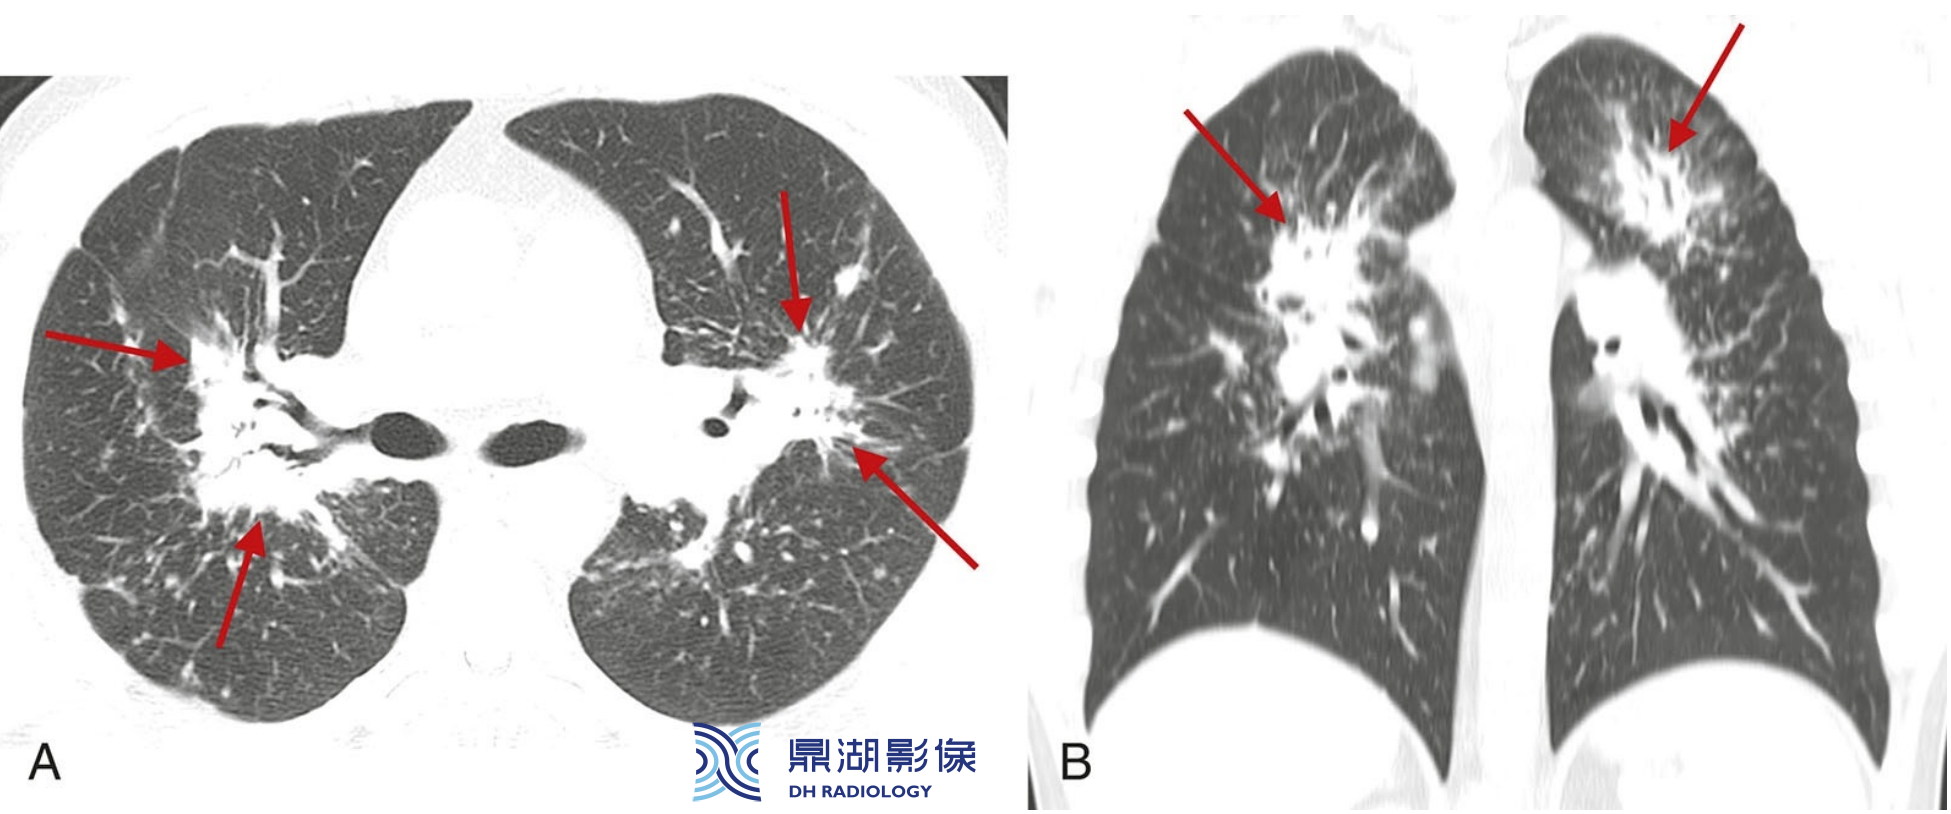

a6e40d7ee5c68dbaf183e07ee5edee07.jpg

结节病的典型表现。

A至C广泛累及肺部的结节病患者,HRCT可见簇状和团块样结节,包绕肺门的动脉、支气管及支气管血管周围间质(红箭,B), 分布于外周支气管血管周围(红箭,A和C) 、肺外周及与叶间裂相邻的胸膜下间质(蓝箭)。